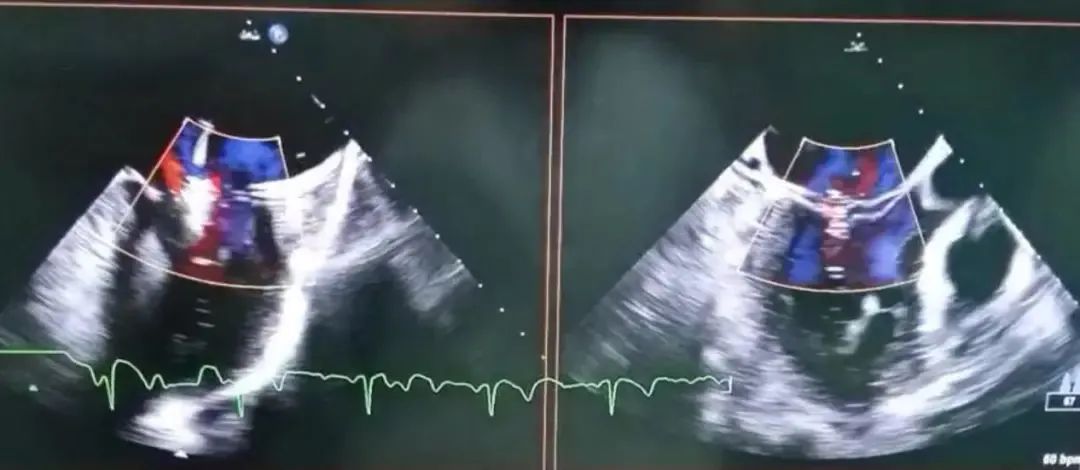

▲术后超声心动图(二尖瓣反流1~2+)